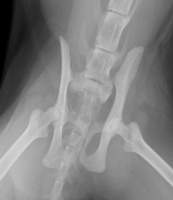

先日、他院の紹介で来院されました猫ちゃんです。もともと野良猫さんなので、外でのアクシデントはつきもの。今回は、交通事故でしょうか、後肢が使えず来院されたそうです。

X 線を見せていただいたところ、骨盤の仙腸関節が左右で脱臼していることが判明、不幸中の幸いでしょうか、ほかの骨折は見当たりませんでした。数日間体調を確認してから、手術を行いました。腰の左右2ヶ所から整復した骨を無事留めることができました。仙骨というしっぽの付け根に当たる骨(中に太い神経が走っています)を、骨盤に左右からスクリューで留めることは、本来難しい手技ですが、今回はきれいに入れることができました。仙骨付近は、神経の分岐部が多くあるため、その後排尿障害や後枝麻痺など後遺症が残ることもあります。

数日して自宅安静で退院となりましたが、その際診察台からキャリーケースに普通に歩いていったのをみて、安心しました。今後は、室内で飼育していただけることになったので、こういった怪我もしなくなると思います。自宅のトイレでおしっこもできました。よかったね、ダヤンちゃん!

来院時、痛くてかなり鳴いていました・・・仙骨と骨盤が外れています。 | 左右からスクリューとピンで留めました。かなり安定して、痛みも数日でなくなったことでしょう。 |